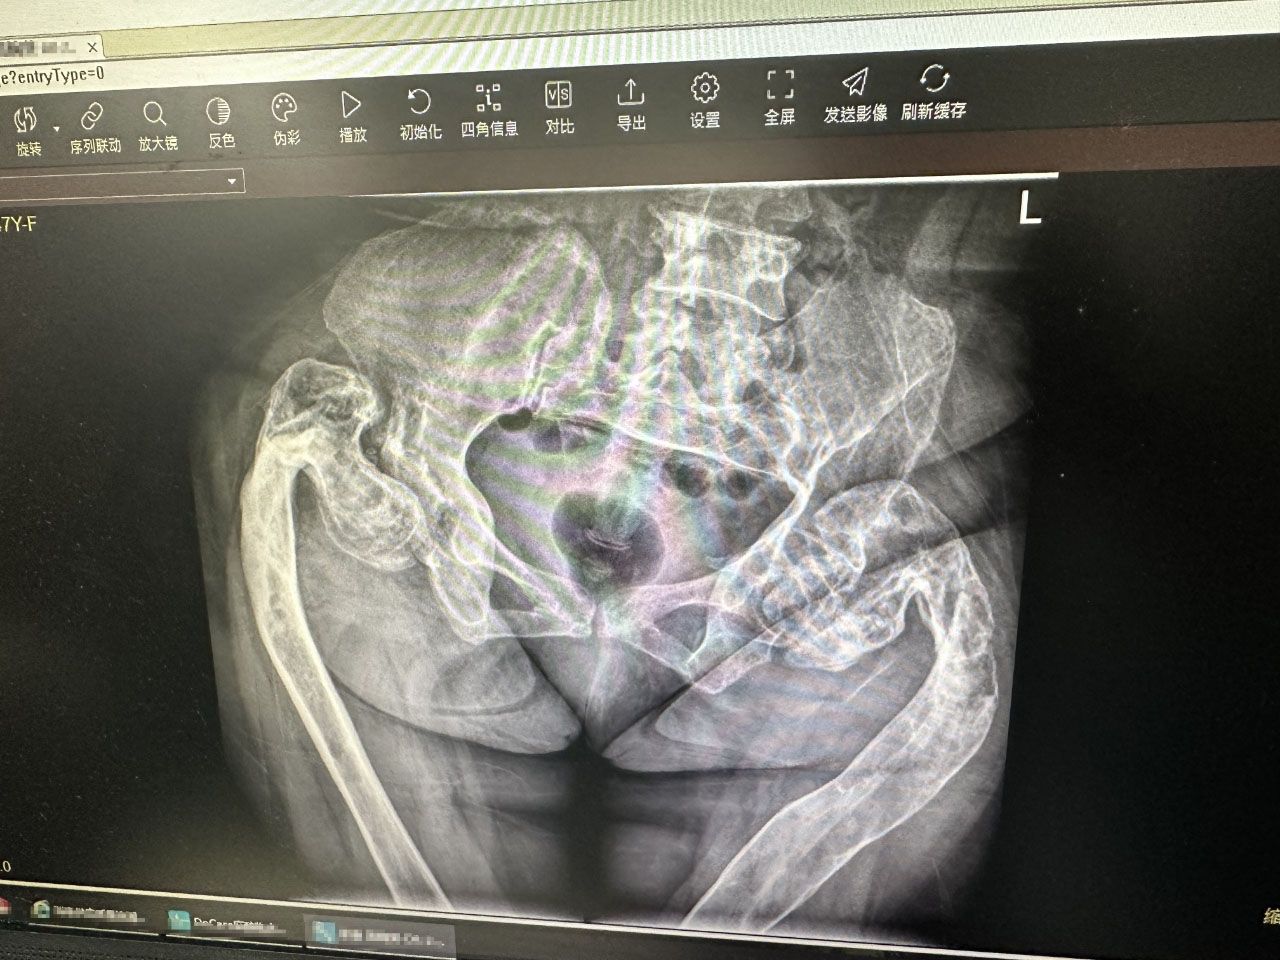

After the welcome ceremony, Prof. Freude and the team of Director LIANG Haobiao immediately engaged themselves in disussion on difficult cases and checking of patients in the wards. The inpatient cases at the moment amounted to 56, indicating a huge workload for the week but also a fruitful outcome of this visit. Director LIANG shared a polytrauma case involving pelvic fractures, traumatic shock and bladder rupture with Prof Freude. Then they discussed how they would select the approach and the sequence of reduction and reconstruction for such cases during surgeries. They also shared their views on the management of the patient's bladder and urinary tract infections, which in this case, already affected the treatment of the pelvic fracture.

In between one difficult case discussion, Prof. Freude noticed that there is an anatomic structure difference in the pelvis between Chinese people and Europeans, especially Germans, which is the difference in shape and thickness. He proposed to conduct a multi-centre double-blind controlled study with Director LIANG's team in this spot. He detailed that each of them can collect a certain number of cases for comparative study in their own centre, and the effective results obtained could be published in international journals. If this works, the research result would not only expected to contribute to the development of the scientific research programs of Guangzhou University of Traditional Chinese Medicine Dongguan Hospital (Dongguan Hospital of Traditional Chinese Medicine), but may also provide important references for further studies on treatment of pelvic fracture reduction in different ethnic groups and even for subsequent development of related implants.

In the morning of April 9, Prof. Freude and Director LIANG Haobiao joined the OR and performed a pelvic fracture ORIF surgery with pararectus approach. They discussed and planned the surgery in detailed the day before and checked the patient's body.